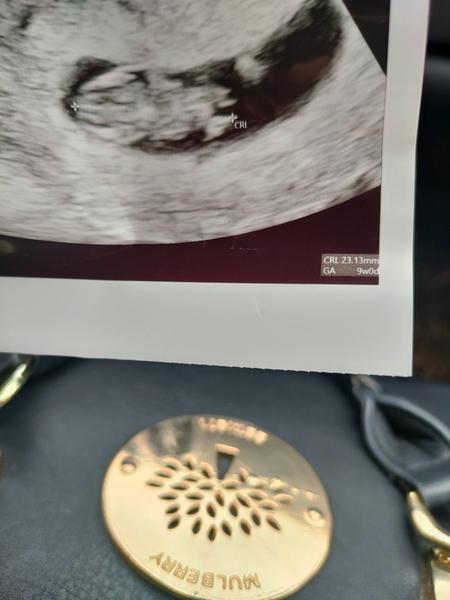

Ahojte.takja som dnes podla ms 6+2 a podla ovu 5+4, bola som dnes u dr a na sone videl akurat tak prazdnu dutinku v maternici, ze to je este skoro nieco vidiet :( tak neviem ci je to ok alebo nie ked niektore uz maju srdiecko a ja etse ani plod :(

@bejka90 neboj dobre b7de buduci tyzden uz bude srdiecko ja som bola 5+6 boli vidno len plod bez akcie potom som sla do centra 6+0 a srdiecko bilo ako zvon takze ono sa to moze velmi rychlo zmenit dne videl vacok zajtra by uz mozno videl aj plod pidlq ovu si len 5+4 este ma cas sa objavit 🥰😍držím prsty 😍

@zojeva hej nosom zvedava co tebe povie potom pis 🙂 kontrola neviem zajtra mam volat na vysledok krvi a tak sa dohodneme..ale som vravela sestricke ze s auz tak nemusi ponahlat s terminom bo uz chcela ze o 2tyzdne tak jek vrvaim ze kludne aj 3 sle nech uz je tam aj srdiecko ked bude vsetko v poriadku nech tam neslapem kazde2 tyzdne jak na klavir :(

baby ja som v 6tt is ste nemala ❤️, az v 7. no stresss 🙂

a inak datum nemam ani podla ms ani ovu. proste sa uhniezdilo nejak neskor a dokonca mi na druhej kontrole v 13tt zmenila datum porodu. oni to odhaduju potom podla velkosti, nerobte si z toho vobec hlavu 🤪 pokym je to par dni nic sa nedeje 🙂